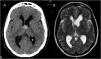

An extremely rare complication of endoscopic colloid cyst removal is presented. Terson’s syndrome related to endoscopic resection of a colloid cyst has been reported only twice before in the literature and it could be explained by intracranial hypertension related to rinsing during the procedure. The case is described and the complications in the neuroendoscopic removal of colloid cyst are reviewed from the literature.